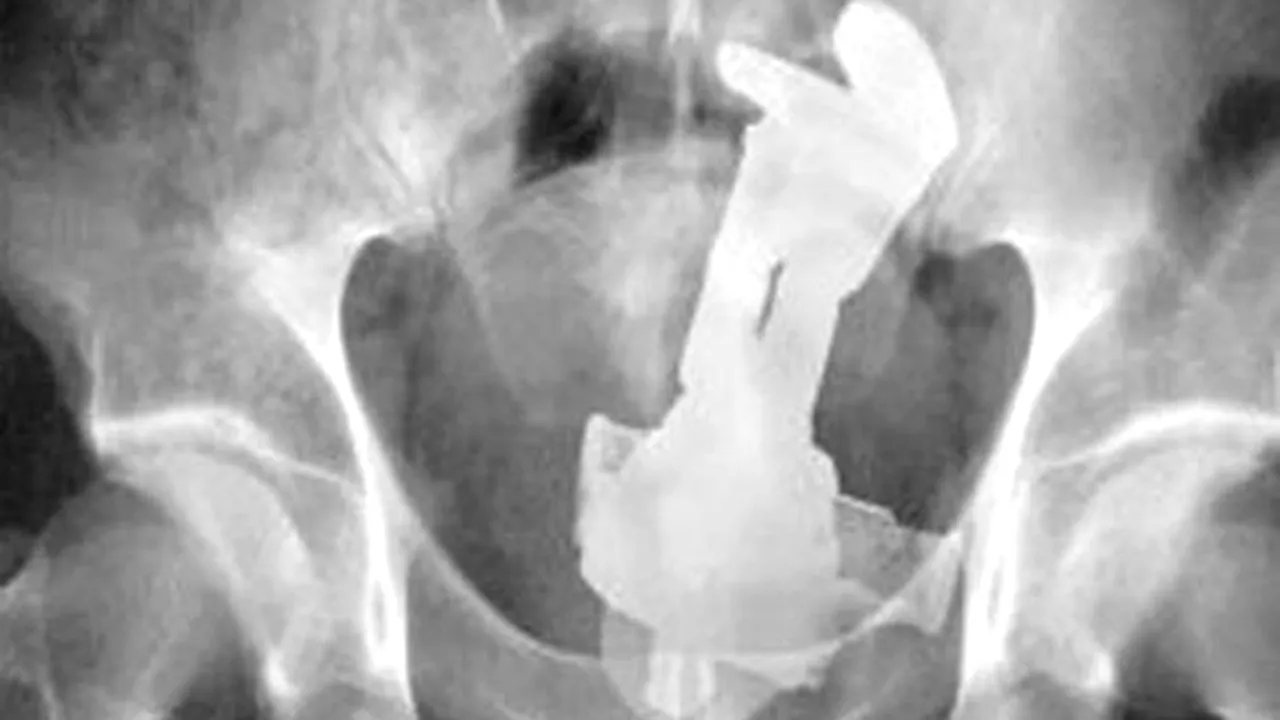

The Sun publică o galerie foto cu unele dintre cele mai înfricoșătoare radiografii din istorie.

În imagini, se pot observa oameni care au ajuns la urgențe cu cuțite, chei, cuie, cârlige și alte obiecte tăioase înfipte în ochi, față sau alte părți ale corpului. Cu toate acestea, victimele au supraviețuit.